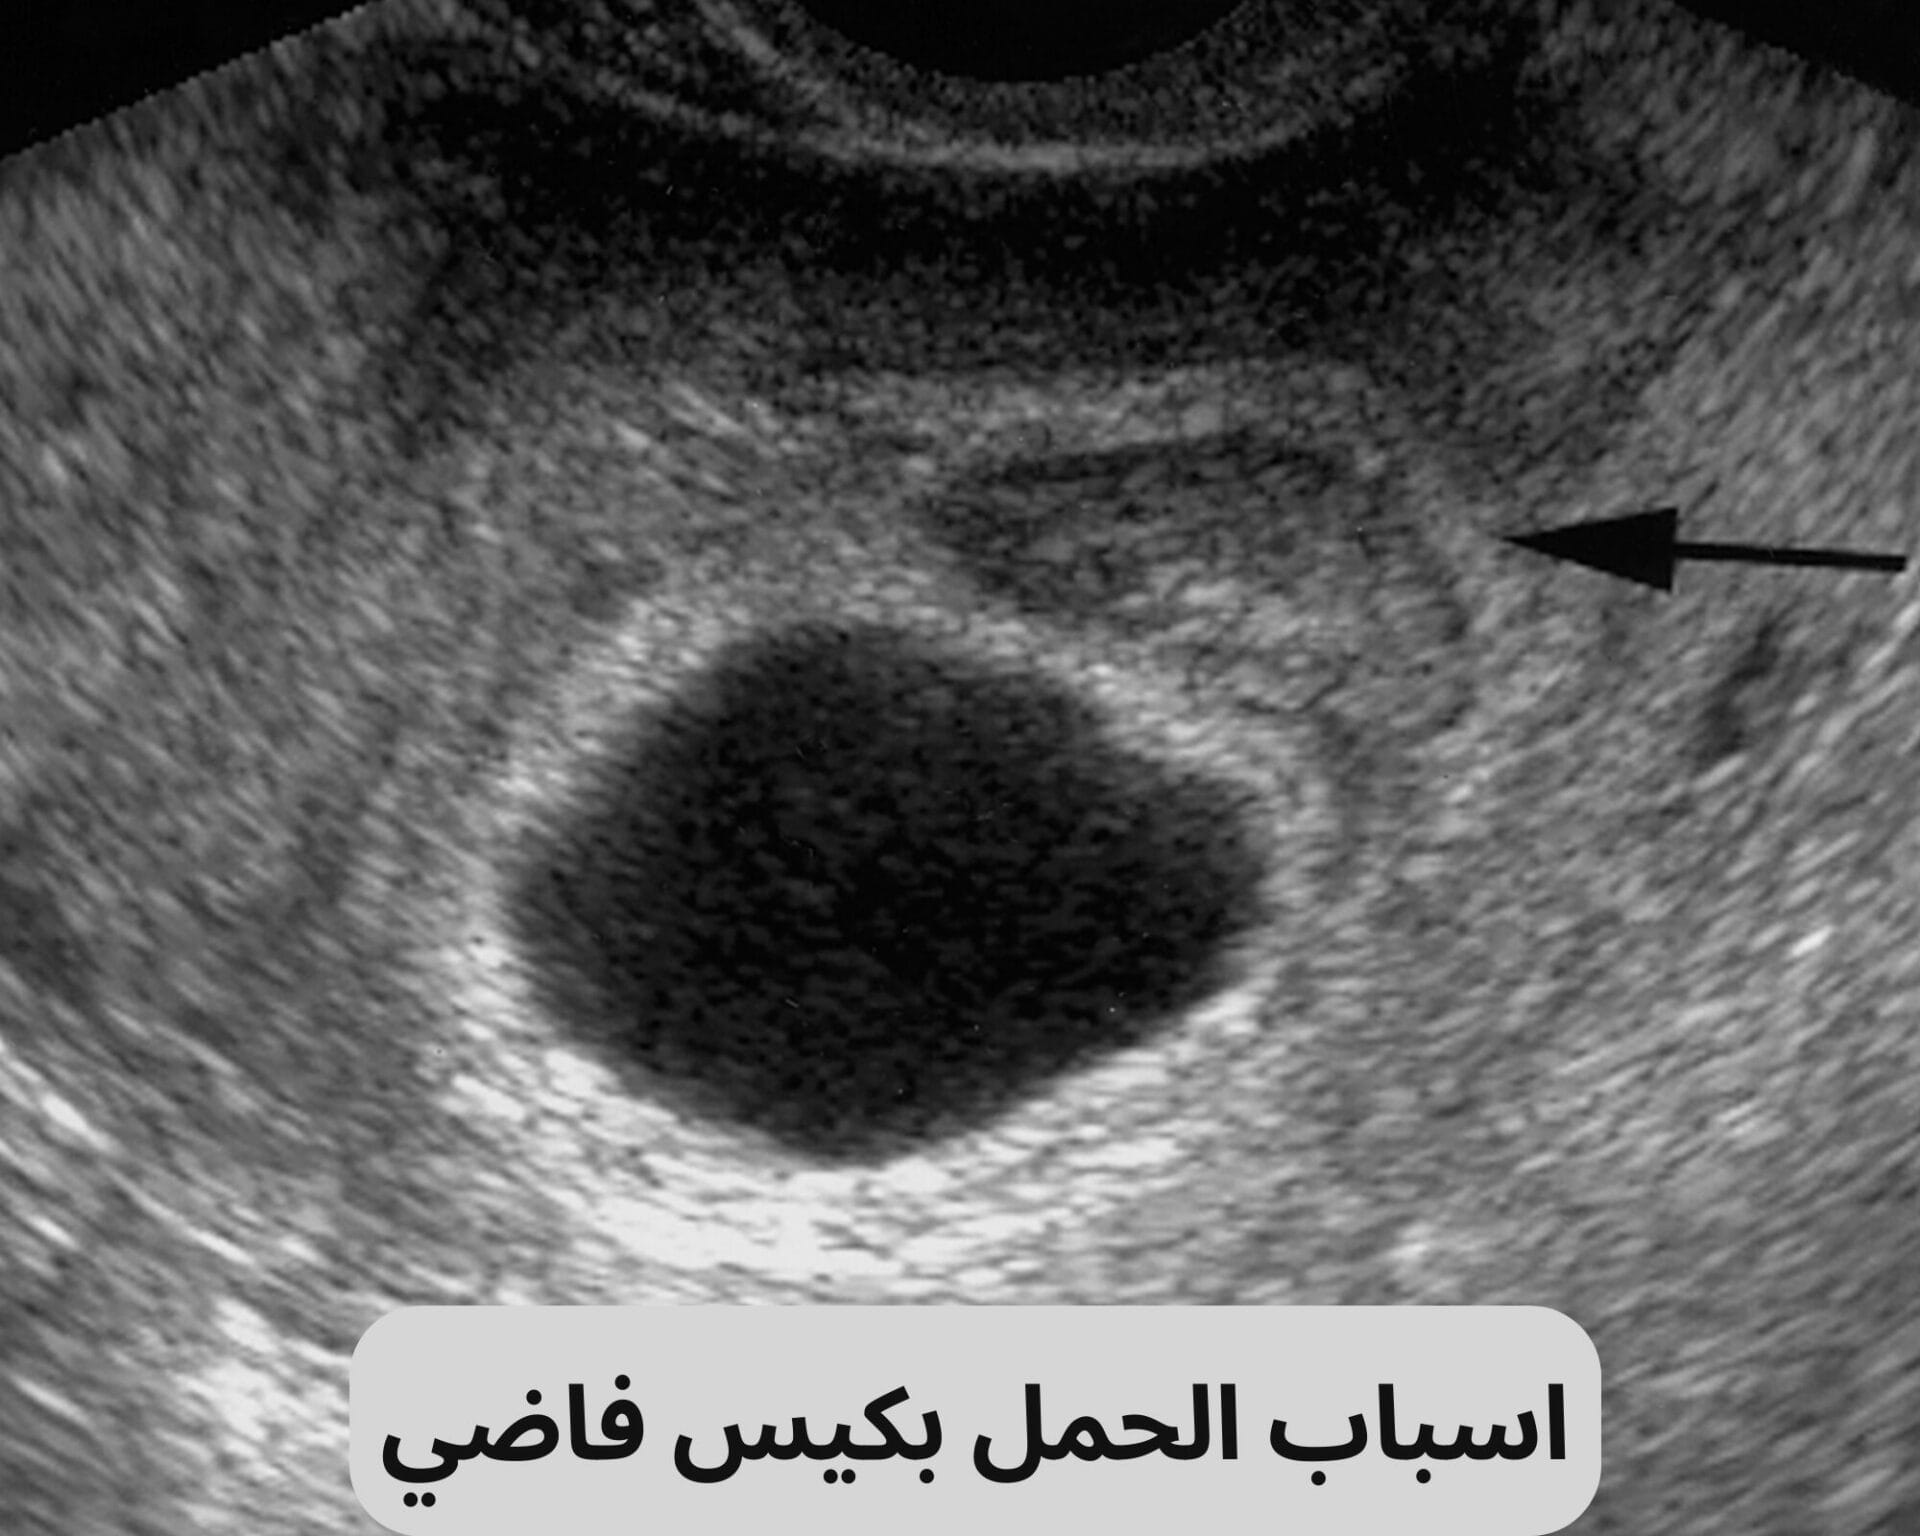

الحمل بكيس فاضي: اسبابه وأعراضه وفرص الحمل الطبيعي بعده

الحمل بكيس فاضي هو حالة نادرة تحدث عندما يتشكل كيس فاضي في الرحم بدون وجود جنين داخله. في هذه الحالة، يتطور الكيس الأولي (المشيمة) بشكل طبيعي، ولكن لا يتطور الجنين. يعتبر الحمل بكيس فاضي نوعًا من إجهاض المفرط، حيث أن جسم المرأة يظهر علامات حمل مثل زيادة مستوى هرمون β-hCG، لكن صورة الموجات فوق الصوتية تظهر افتقارًا لأية هيئات جنينية. قد تظهر أعراض مثل نزف وآلام شبيهة بآلام الحيض.

يشير الحمل بكيس فاضي إلى حالة نادرة تتميز بتشكل كيس فاضي في الرحم دون وجود جنين داخله. يعني ذلك أن المشيمة تتطور بشكل طبيعي، لكن لا يحدث تطور للجنين. رغم أن المرأة قد تعاني من أعراض الحمل المبكرة وزيادة مستوى هرمون β-hCG في الدم، إلا أن صورة الموجات فوق الصوتية تظهر عدم وجود جسم جنيني في الكيس. تصاحب هذه الحالة أعراض مثل نزف خفيف وآلام شبيهة بآلام الحيض. يعود التشخيص دقته إلى الفحص الطبي بالموجات فوقَ صَوتِيةٍ عفْويةٍ واختبارات من قِبَلِ مُخِتَصِّ هذا المجال. من المهم مشاركة قصَّةٍ سابقة لأى استخدامات بروجسترون أو استفاءَ بأعشاب التي رُبِمَا استَعْمِلَتْ في محاولةٍ لزيادَةِ فُرص الحمل